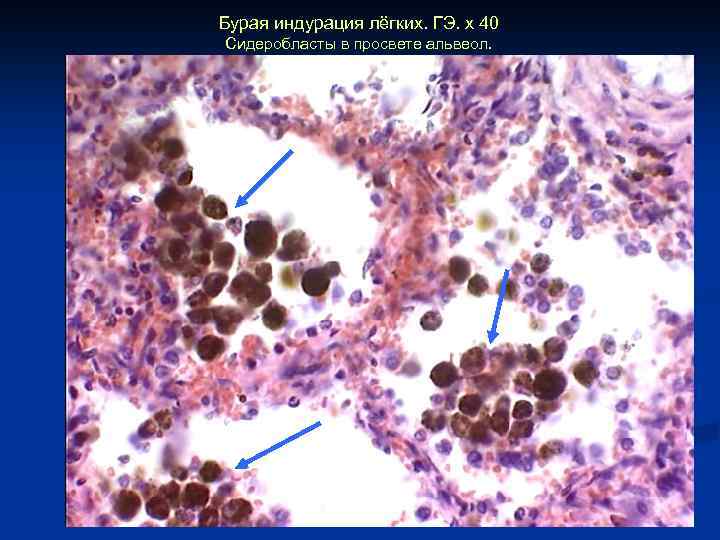

Бурая индурация лёгких. ГЭ. х 40 Сидеробласты в просвете альвеол.